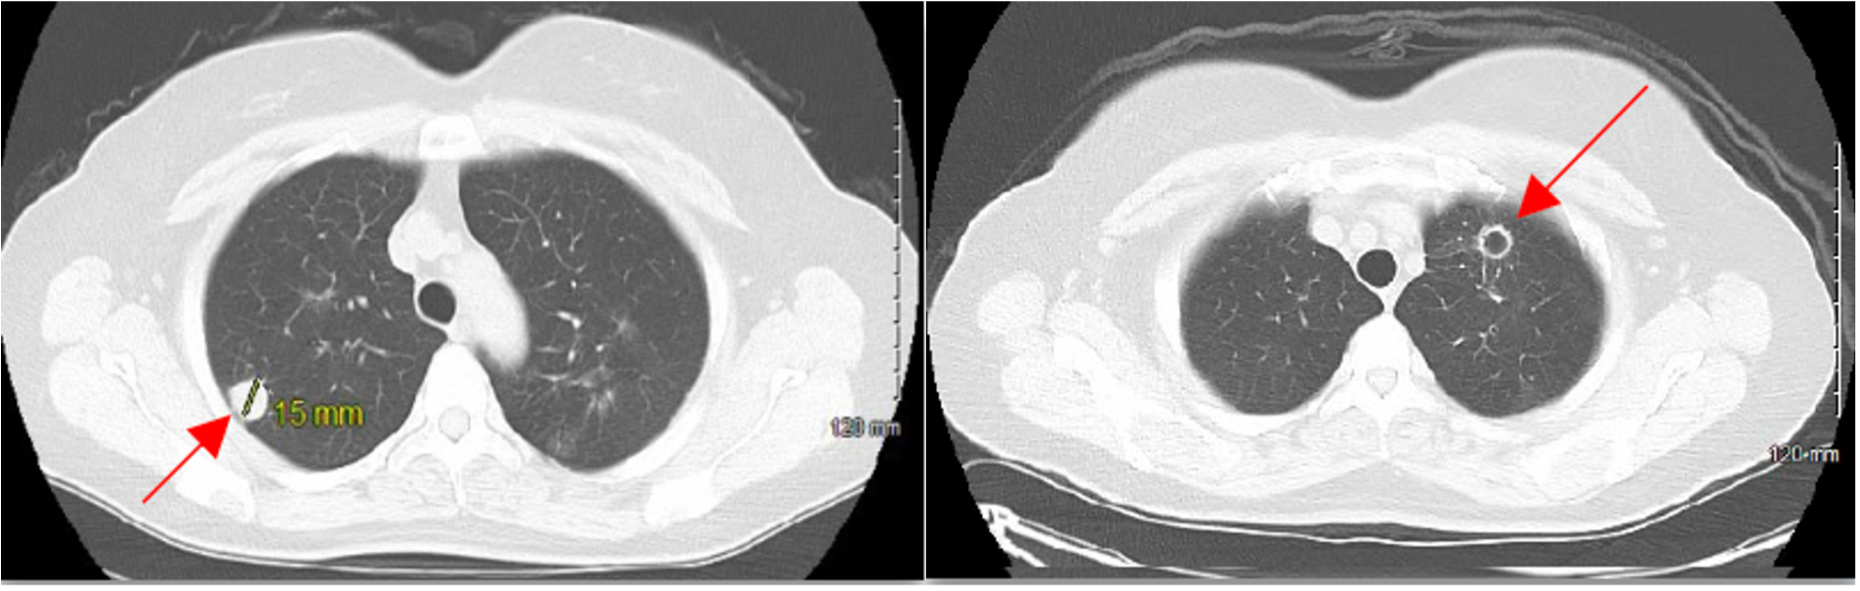

Case Presentation: 54-year-old female with past medical history of bronchitis was referred for evaluation of hemoptysis and chest radiograph changes. She had 5 pack year history of cigarette smoking but quit 4 years prior. Additionally, she admitted to significant occupational exposure working as an electrician for 8 years. On physical examination, her temperature was 37.3°C, blood pressure was 126/77 mmHg, heart rate was 85 beats per minute, and oxygen saturation was 94% on room air. Her lab values were significant for a positive QuantiFERON test; negative antineutrophil cytoplasmic antibodies (ANCA) and antinuclear antibodies (ANA) tests.Computed Tomography (CT) scan of chest revealed multiple bilateral pulmonary nodules with some cavitation. The largest solid nodules measured 13 mm and 15 mm in the left and right upper lung, respectively. A CT-guided biopsy was performed on a right lower lobe nodule which revealed non-neoplastic chronic inflammation with an area of geographic necrosis. An additional robotic-assisted left upper and lower lobe wedge resection was performed revealing white to tan granular lesions with necrotizing granulomatous inflammation and lymph nodes with anthracosis and abundant histiocytes consistent with GPA.Following rheumatology consultation, the patient was treated with intravenous rituximab once weekly for 1 month, followed by once a month for 6 months. A repeat CT scan done 4 weeks following treatment showed no development of new lesions and size reduction or resolution of previously noted nodules.